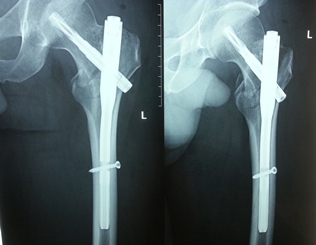

燕化医院开展手术治疗四肢、骨盆骨折患者取得了良好的效果。股骨颈骨折一般以全髋关节置换(THA)和半髋关节置换为主;而对于股骨转子间骨折的外科治疗多采用内固定手术,包括锁定钢板;动力髋系统即DHS、PFN(A)。具有创伤小(微创)、内固定牢固、术后恢复快便于提早下地活动等优点。肱骨、尺桡骨、股骨干、胫骨干的骨折主要采用带锁髓内钉和锁定钢板治疗;复杂的骨盆骨折则采用切开复位,重建钢板治疗。

图2.髓内钉 PFN(A)内固定术后